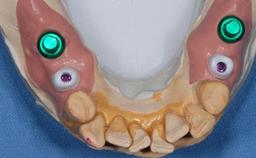

The patient presented with a failing tooth-supported fixed dental prosthesis with cantilever extension replacing the right maxillary central incisor. His chief presenting complaint was poor esthetics, in particular the dark discolored margin around the abutment tooth, the maxillary left central incisor. He reported a history of trauma at a young age, which necessitated the replacement of his maxillary right central incisor as well as root canal therapy of the adjacent left central incisor. The existing prosthesis had been in situ for over 20 years. The initial periapical radiograph displayed good proximal bone levels at the adjacent teeth and a wide incisive canal, which was a concern. The left central incisor presented a very wide root canal treatment with compromised radicular dentin thickness, which was a consideration in the decision between a new tooth-supported fixed dental prosthesis vs. an implant-supported prosthesis. After a lengthy discussion on the risks and benefits of both treatment options, the patient decided on a single-tooth implant replacement.

Bone Augmentation Simultaneous

Augmentation Materials Xenogenous

Abutment Type Customized

Prosthesis Type FDP